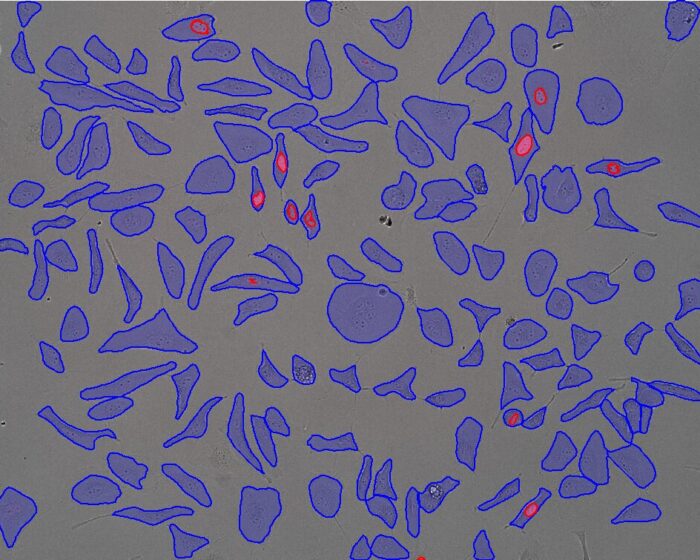

- Biomedical

- Cancer Research

- Cell Biology

- Histology/Pathology

- Life Science